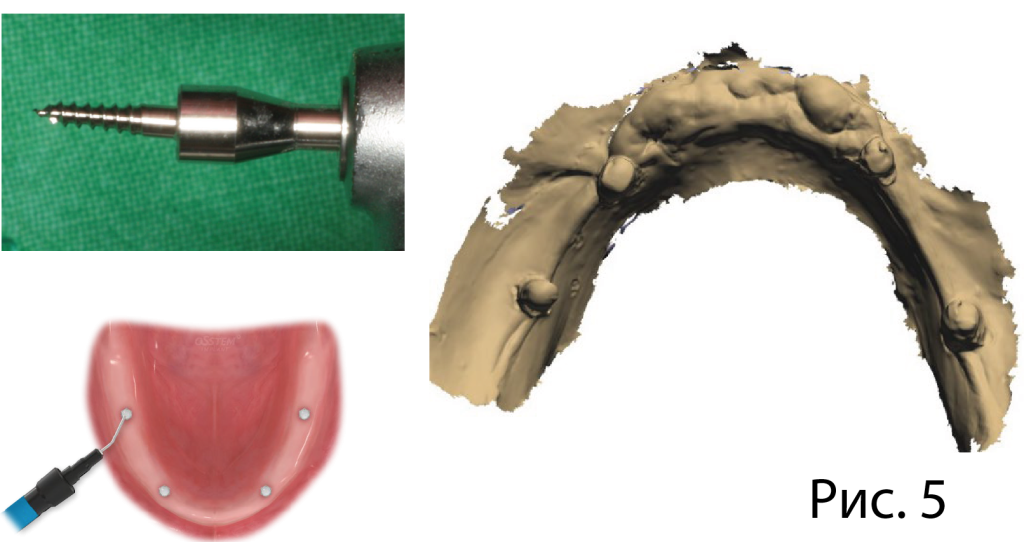

3) Сопоставление данных (по коронкам зубов на верхней челюсти и по ортодонтическим винтам Osstem на беззубой нижней челюсти).

Данные интраорального сканирования и КТ сопоставляются в программе Implant Studio (3Shape). На верхней челюсти в качестве ориентира используются 6 зубов, на которые также будет опираться хирургический шаблон. На нижней челюсти с этой целью наносят текучий композит на шляпки ортодонтическоих винтов Osstem.

5.png